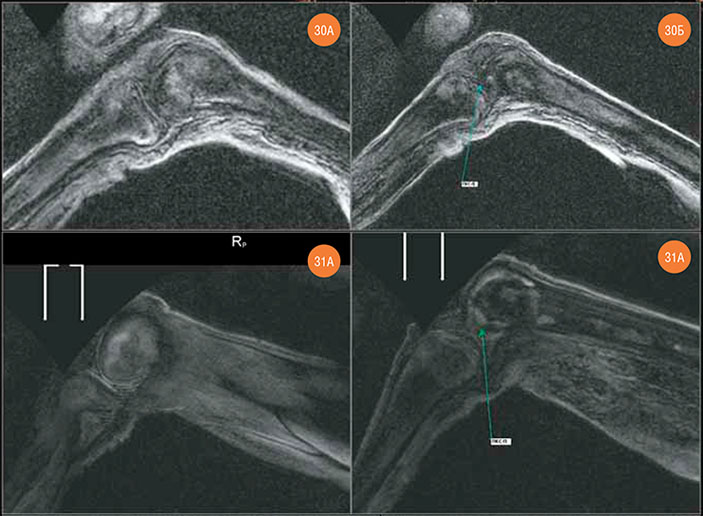

Рис. 27. Строение крестца. Рис. 28. Левое бедро. В дистальной части диафизирной полости — отечно-склеротические очаги. Рис. 29. Правое бедро. А и Б — параллельные срезы. В дистальной части диафизирной полости — отечно-склеротические очаги

На левом коленном суставе можно отметить элементы субхондрального склерозирования и сфероидные отечные очаги диаметром 4–13 мм в проксимальном эпифизе левой большеберцовой кости. Передняя крестообразная связка правого коленного сустава деформирована и утолщена, вероятно, в результате прижизненной травматизации.

Рис. 30. Левый коленный сустав. А — элементы субхондрального склерозирования и сфероидные отечные очаги в проксимальном эпифизе левой большеберцовой кости. Б — визуализируется достаточно сохранная передняя крестообразная связка (ПКС, показана стрелкой). Рис. 31. Правый коленный сустав. А — достаточно сохранный латеральный мениск. Б — передняя крестообразная связка (ПКС, показана стрелкой) — деформирована, утолщена, но ее форм-фактор сохранен